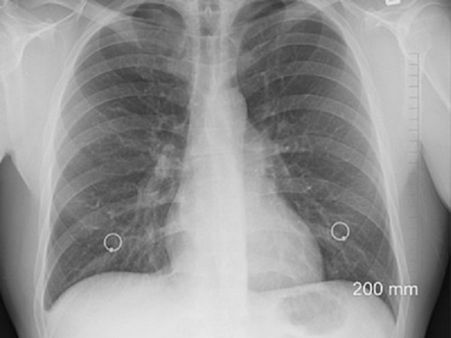

Diagnosis Of Pneumothorax

- Physical examination: Here, the medical expert will ask questions about the history of lung disease, trauma or accident.

- Arterial blood gas test: To measure the amount of carbon dioxide in the blood. Low levels of oxygen and high levels of CO2 indicates pneumothorax.

- Imaging tests: It includes a CT scan, ECG or X-ray to confirm pneumothorax.